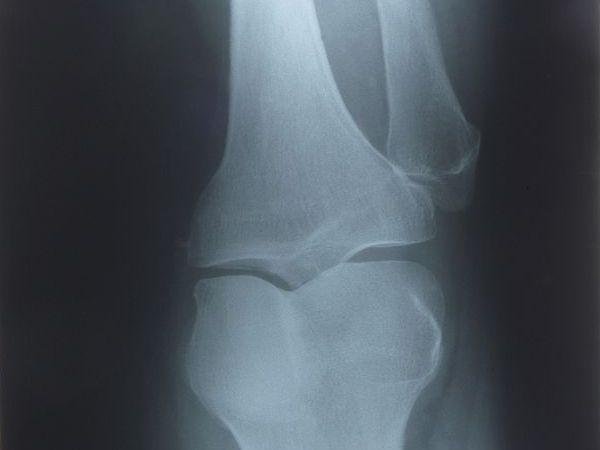

消炎加促進軟骨生長 有效治療退化性關節炎

退化性關節炎屬於發炎性疾病,並非老年人才會罹患,雖每個人都會老化,但僅約30%的人才會罹患退化性關節炎;台灣運動醫學會榮譽理事長葉文凌指出,退化性關節炎是指關節內所有構造,出現發炎、損壞等綜合性表現,患者最常出現疼痛等症狀。X光片檢查 恐怕無法找出疼痛關鍵診斷上,通常會透過照X光片方式,

>>看全文... 消炎加促進軟骨生長 有效治療退化性關節炎